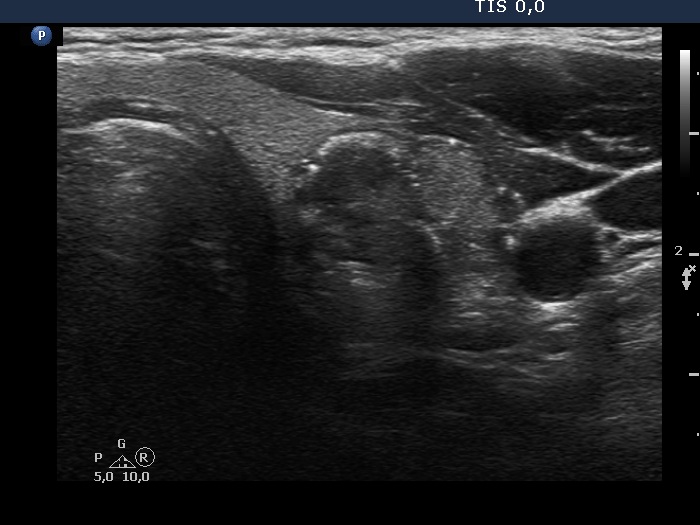

Ultrasonography. The thyroid was echonormal. There was a dominantly hypoechoic nodule in the left lobe. The nodule had both microcalcifications and macrocalcification and was avascular.